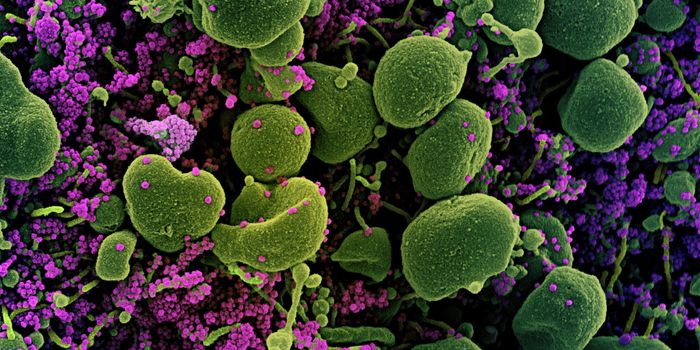

APR 01, 2020MicrobiologyThere are a couple of different kinds of tests that researchers will be developing and clinicians will be using to disru ...

MAY 03, 2020Genetics & GenomicsThe origin of SARS-CoV-2, the pandemic virus that causes COVID-19, has become politicized as leaders seek to place blame ...

APR 06, 2020Genetics & GenomicsSARS-CoV-2 is the name for the pandemic coronavirus that causes the illness COVID-19, which affects people in extremely ...